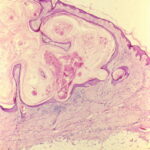

Kerato acanthoma Proliferating phase early development = القرنوم الشائك مرحلة مبكرة

The histopathologic features of keratoacanthoma depend on the stage of evolution of the tumor. In early, proliferative lesions, the epithelium is markedly hyperplastic, and the central keratotic plug is not as pronounced as in fully developed lesions. The lesion has an overall symmetric aspect . Although atypical cells do not represent the majority of the cells in typical keratoacanthoma, there may be atypical keratinocytes and mitoses, especially at the lower margin of the tumor. Nests of epithelial cells may detach from the main tumor mass and be found in the superficial reticular dermis. Fully developed, mature lesions are characterized by a large central core of keratin surrounded by a well-differentiated proliferation of squamous epithelium that in some cases may resemble squamous cell carcinoma . The epidermis at both sides of the central core extends over the keratotic area in a fashion that has been described as “lipping” or “buttressing,” giving a distinct crateriform appearance to the lesion. Nests and strands of keratinocytes may be found apart from the main bulk of the tumor but usually do not extend lower than the level of sweat glands .